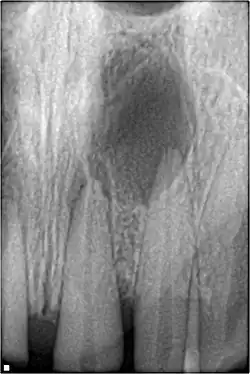

Pulpal obliteration

4–24% of traumatized teeth will have some degrees of pulpal obliteration that is characterized by the loss of pulpal space radiographically and yellow discolouration of the clinical crown. No treatment is needed if it is asymptomatic. Treatment options will be extraction for symptomatic primary tooth. For symptomatic permanent tooth, root canal treatment is often challenging because the pulp chamber is filled with calcified material and the drop-off sensation of entering a pulp chamber will not occur.[44]